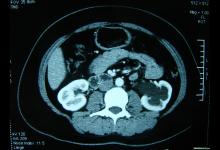

肾结石又叫做尿路结石,是尿中多余的矿物质结晶后在肾脏(约占90%)里沉积,最终形成肾结石。民间老偏方网为您收集...

肾结石是泌尿系统常见疾病之一,属中医学“石淋”、“砂淋”及部分“血淋”、...